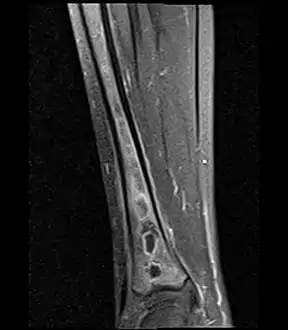

- Fat saturated STIR (short tau inversion recovery) image showing hyperintense edema in the calf musculature, marrow edema, and subperiosteal pus. The intramedullary abscess cavity is hyperintense as well.